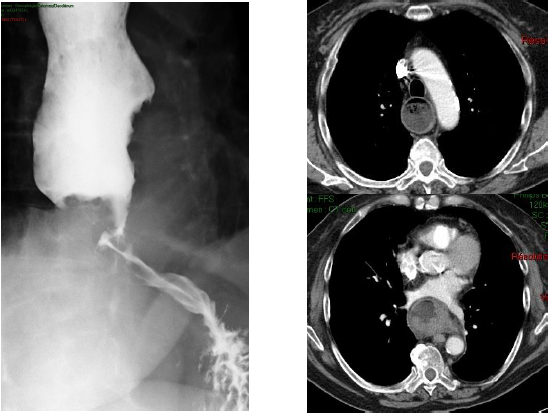

Tumeurs du tube digestif en imagerie